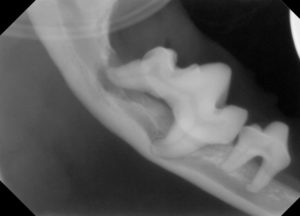

3.レントゲンでは、顎の骨が歯周病により骨折しやすい状態が確認されます。

5.下顎の骨が溶けて、骨折しやすくなっています。